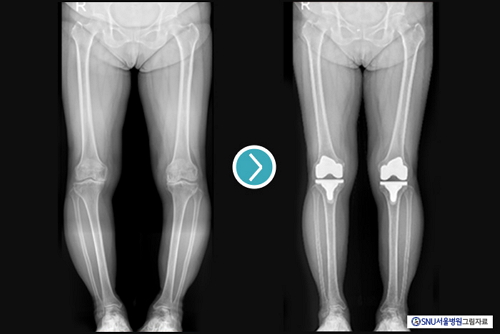

¹«¸ Àΰø°üÀý ġȯ¼úÀº ÅðÇ༺ °üÀý¿° ȯÀÚÀÇ ÅëÁõÀ» ÁÙÀÌ°í º¯ÇüÀ» ±³Á¤ÇÏ¸ç °È±â µîÀÇ ±â´ÉÀ» °³¼±ÇÏ¿© »îÀÇ ÁúÀ» ³ôÀÌ´Â ÁÁÀº ¼ö¼úÀÌ´Ù. ±×·¯³ª ¼ö¼ú¿¡ Ưº°ÇÑ ¹®Á¦°¡ ¾ø´õ¶óµµ, ¼ö¼ú ÈÄ ¼Ò¼ö¿¡¼ ºÒÆíÇÏ°í ºÒ¸¸Á·½º·¯¿î »óȲÀÌ »ý±æ ¼ö ÀÖ´Ù. ÀÌ·¯ÇÑ »óȲÀ» Á¶±Ý ´õ ÇØ°áÇϱâ À§ÇÑ ¿©·¯ ³ë·Âµé Áß Çϳª°¡, ÃÖ±Ù °¢±¤¹Þ°í ÀÖ´Â ·Îº¿À» ÀÌ¿ëÇÑ ¹«¸ Àΰø°üÀý ¼ö¼úÀÌ´Ù.

·Îº¿À» ÀÌ¿ëÇÑ ¼ö¼úÀº ÀÇ»çÀÇ ¼ÕÀ¸·Î¸¸ ÇÏ´Â ¼ö¼ú¿¡ ºñÇØ, ¼ö¼ú ÈÄ ±Þ¼º ÅëÁõÀ» ÁÙ¿© ÀçȰÀ» ºü¸£°Ô Çϰí, ¼ö¼úÀÇ Á¤È®µµ¿Í Á¤¹Ðµµ¸¦ ³ôÀ̸ç, ÀδëÀÇ ±ÕÇüÀ» ´õ Àß ¸ÂÃ߸鼵µ ȯÀÚÀÇ ¿ø·¡ ´Ù¸®»ÀÀÇ ¸ð¾çÀ» ¹Ý¿µÇÑ ¼ö¼ú ¹æ¹ýÀ» Àû¿ëÇÒ ¼ö ÀÖ´Â µî ¸¹Àº ÀåÁ¡À» °¡Áø´Ù.